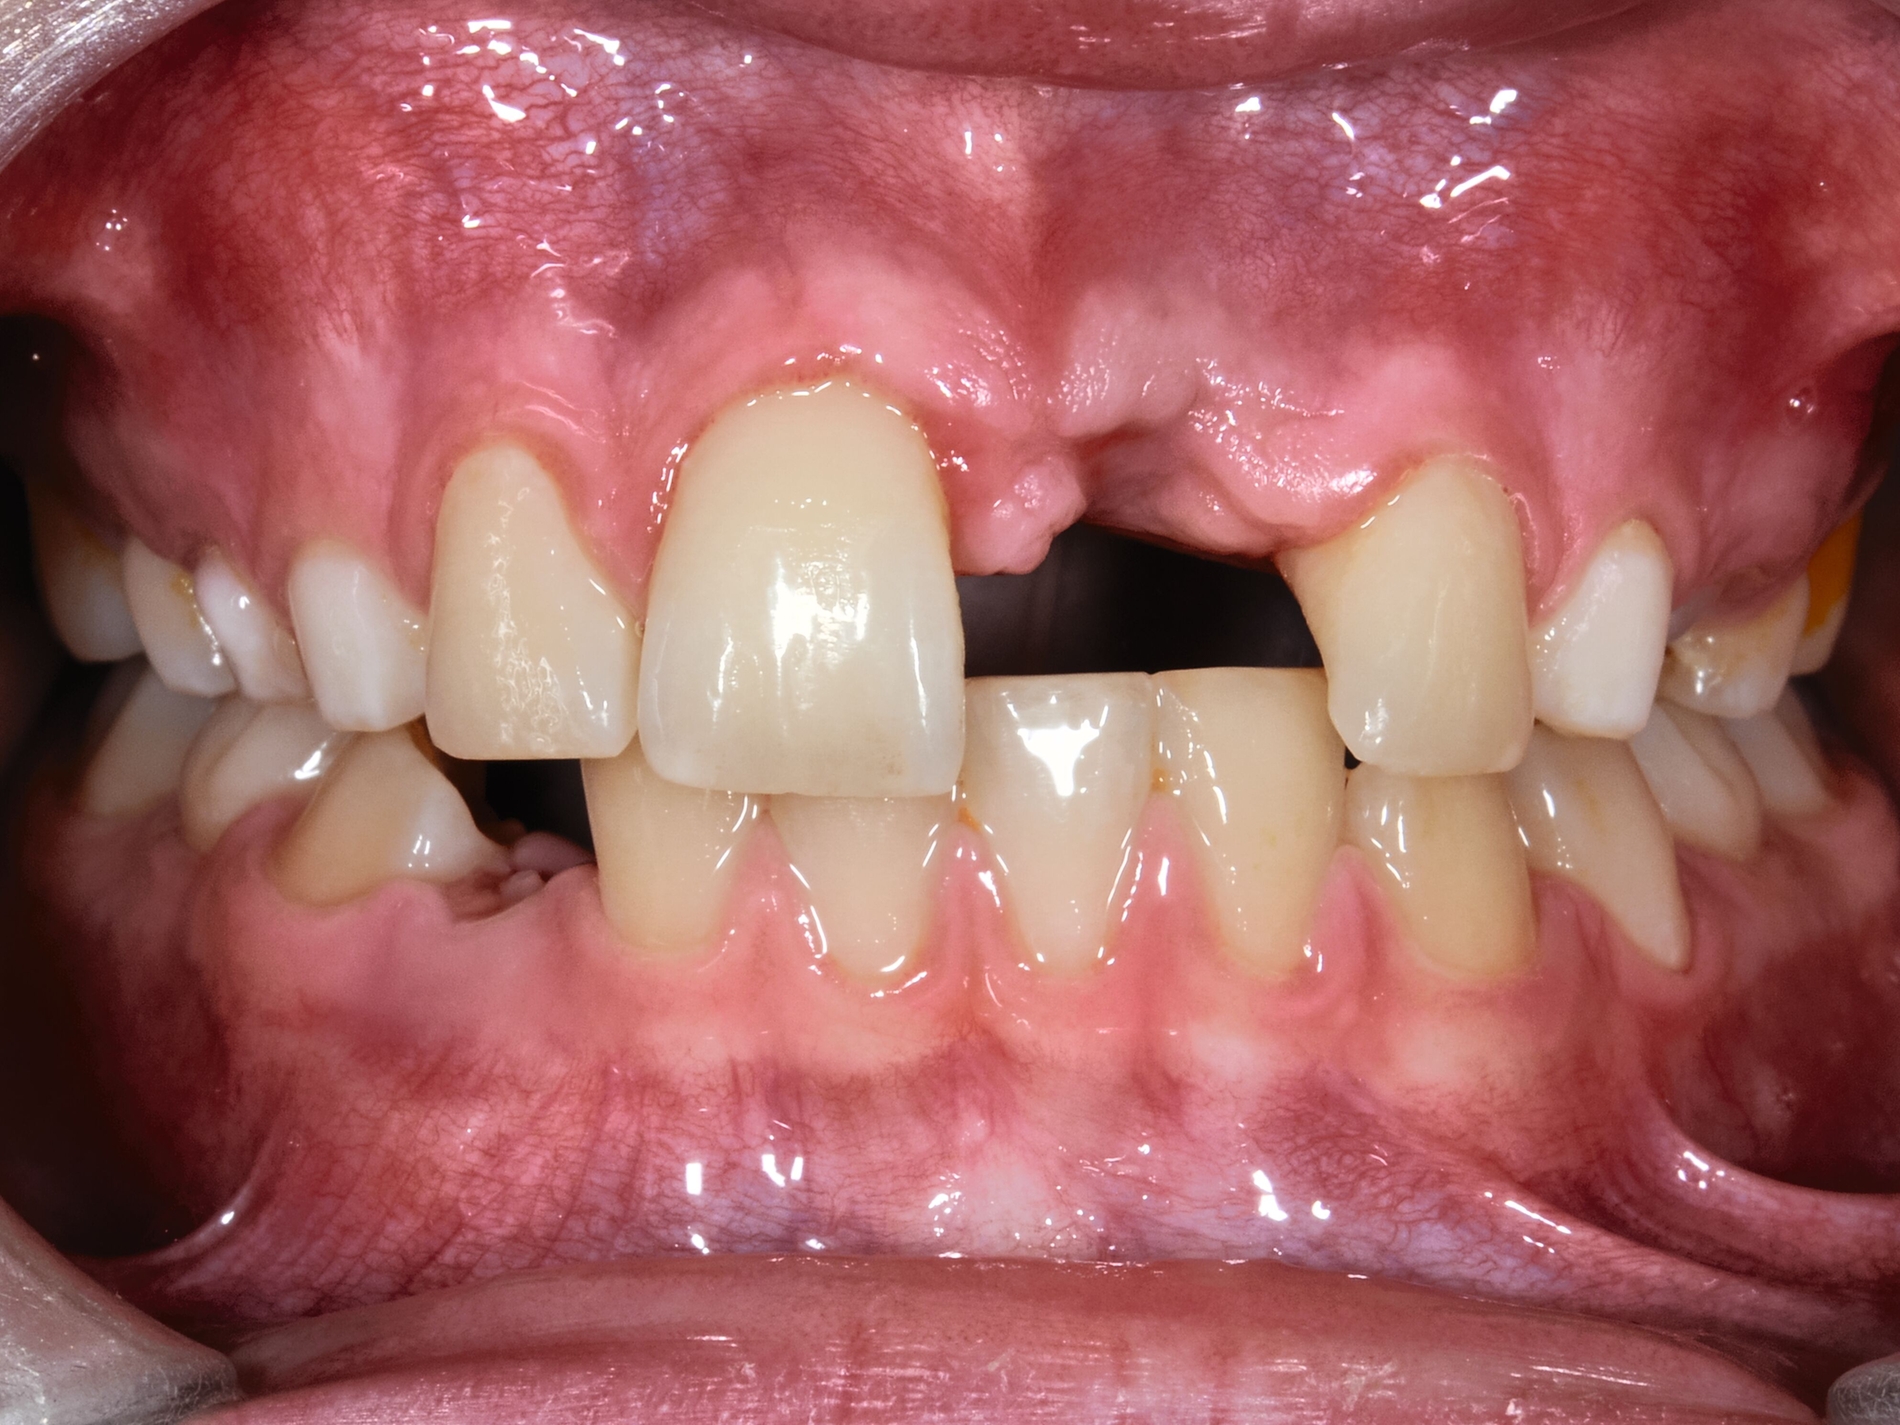

Prävention

Gerade Patienten mit einer stark vergrößerten Frontzahnstufe und einer fehlenden Lippenbedeckung der Schneidezähne können von einer frühzeitigen kieferorthopädischen Korrektur vor der zweiten Wechselgebissphase profitieren [Bauss et al., 2008]. Malokklusionen erhöhen das Risiko für traumatische Zahnverletzungen [Bauss et al., 2008; Corrêa-Faria et al., 2016; O'Mullane, 1973]. Eine kieferorthopädische Behandlung für Kinder mit solchen Merkmalen (Abbildung 1) könnte daher hilfreich sein, um Frontzahntraumata sowie die daraus resultierenden Spätfolgen zu verhindern.

Eine kontinuierlich aktualisierte Serie von Cochrane-Reviews [Thiruvenkatachari et al., 2015; Thiruvenkatachari et al., 2013] zur Behandlung von Klasse-II-Malokklusionen bestätigt aktuell [Batista et al., 2018] den Vorteil einer frühen (zweiphasigen) Behandlung bei der Reduktion der Inzidenz von Schneidezahntraumata.